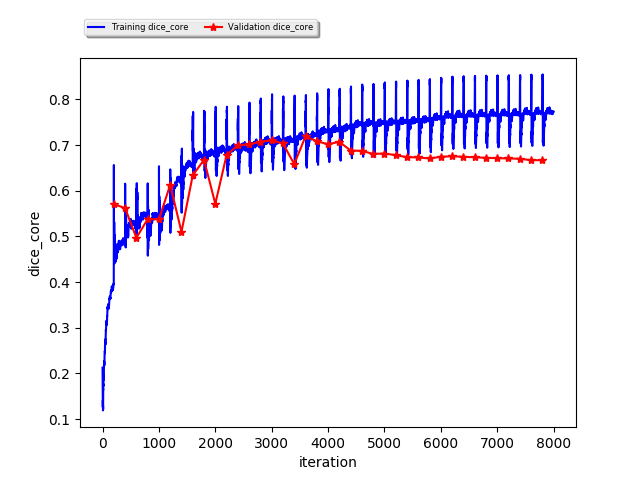

These results can be further analyzed and confirmed with Train/Development curves in Fig. 4, which mostly indicate the generalization power of the method by analyzing the bias/variance trade-off. We clearly see that from epoch 18 (iteration 3600) we start overfitting the tumor core metric (Fig. 4.b) while the other regions are either slowly gaining insignificant improvements (Fig. 4.a, whole tumor) or not improving at all (Fig. 4.c, enhancing core). However the development loss is still improving due to the cross-entropy term.